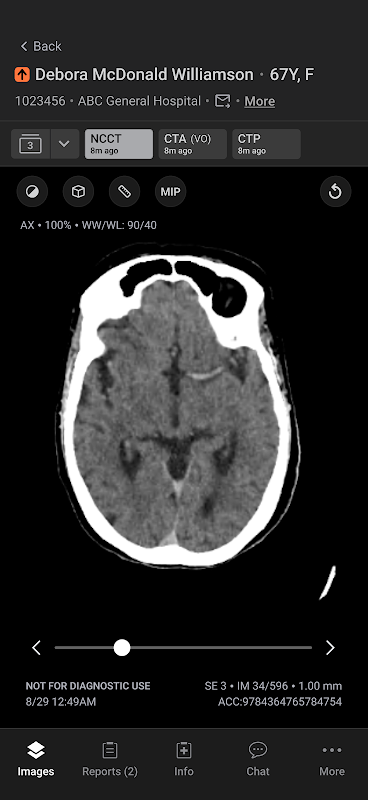

Aplikasi komunikasi mudah alih Aidoc memperkemas komunikasi untuk mempercepatkan membuat keputusan sensitif masa dan meningkatkan kualiti penjagaan. Aplikasi ini menyediakan keutamaan berasaskan AI dan pemberitahuan pelbagai jenis patologi akut termasuk oklusi saluran besar dan embolisme pulmonari.

AI Sentiasa Hidup Aidoc secara automatik mengambil dan menganalisis setiap peperiksaan yang berkaitan untuk mengenal pasti penemuan yang disyaki. Setelah peperiksaan dibenderakan, Aidoc kemudian menyerlahkan penemuan yang disyaki secara langsung dalam aliran kerja pengimejan perubatan. Proses ini memanfaatkan infrastruktur sedia ada dan beroperasi dengan lancar di latar belakang, memproses beribu-ribu peperiksaan setiap hari. Aidoc membantu mengurangkan masa daripada imbasan kepada diagnosis, mempercepatkan kecekapan, masa untuk rawatan dan meningkatkan kualiti penjagaan.